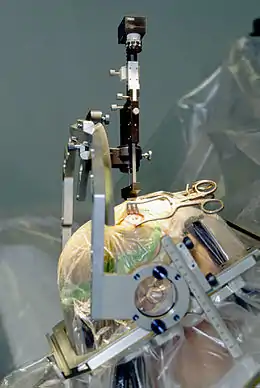

| A person with medication-induced dystonia, which is a byproduct of hypokinesia | |

| Dystonia | A movement disorder characterised by sustained muscle contractions, frequently causing twisted and repetitive movements, or abnormal postures.[8] |